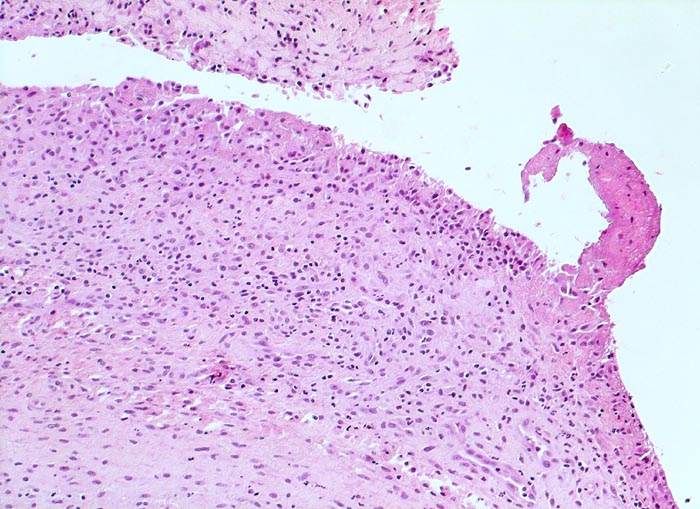

Typische histologische Veränderungen sind eine synoviale Zottenhyperplasie, Verbreiterung der Deckzellschicht unter Einschluss mehrkerniger Riesenzellen, Fibrinexsudate und synoviale Ulzerationen, Infiltrate von Lymphozyten teils in Form von Lymphfollikeln, Plasmazellen, neutrophilen Granulozyten, Makrophagen und Siderophagen, sowie Einschlüsse von Knorpel- und Knochenfragmenten (Detritussynovialitis). Die histologischen Befunde der Synovialis korrelieren oft nicht mit den klinischen Angaben. Trotz fortgeschrittener Gelenkdestruktion mit ausgeprägter klinischer Symptomatik können Synovialektomiepräparate nur sehr geringe pathologische Veränderungen zeigen. Oft ist auch nicht mehr zu eruieren, welche Läsionen Folge der Grundkrankheit und welche Folge diverser intraartikulärer Therapien oder begleitender Superinfektionen sind.

• Synovialis mit verplumpten Zotten.

• Stark proliferierte mehrreihige synoviale Deckzellschicht.

• Herdförmig Fibrinauflagerungen durchsetzt von neutrophilen Granulozyten.

• Hyperzelluläres Stroma mit lymphoplasmazellulärem Entzündungsinfiltrat mit Ausbildung von Lymphfollikeln.